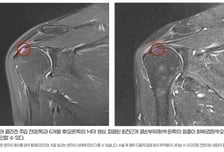

어깨 통증 주범 '회전근개 파열'…'이것' 넣자 83%서 힘줄 되살아나

어깨 통증의 주요 원인질환이 회전근개 파열이다. 이 병은 어깨 관절을 지탱하는 4개의 힘줄(극상건·극하건·소원건·견갑하건)을 과사용했거나 이곳이 충격받으면서 손상당해 발생한다. 특히 어깨뼈(견봉)와 부딪히는 극상건의 손상이 가장 흔하다. 회전근개는 한 번 파열되면 시간이 흐를수록 범위가 넓어진다. 초기 부분 파열 단계에서의 치료가 예후를 가르는 이유다. 실제 2022년 미국 유타대학교 연구에 따르면, 20년 동안 보존적 치료를 받은 부분 파열 환자의 42%는 파열 크기가 커졌으며, 29%는 힘줄이 완전히 끊어지는 '전층 파열'로 악화했다. 이런 가운데, 최근 힘찬병원 관절의학연구소가 회전근개 부분 파열 환자를 대상으로 시행한 '힘줄 내 인체 유래 콜라겐 주입술'의 임상 및 구조적 효과를 분석한 연구결과를 발표해 눈길을 끈다. 이번 연구는 통증 완화, 기능 개선을 넘어 MRI(자기공명영상)를 통해 힘줄의 구조적 변화까지 평가했다는 점에서 주목된다. ━콜라겐 주입술로 '힘줄의 구조적 회복' 효과 입증━힘찬병원 정형외과 연구팀은 6주 이상의 보존적 치료에도 호전되지 않은 극상건 부분 파열 환자 30명(평균 연령 61.